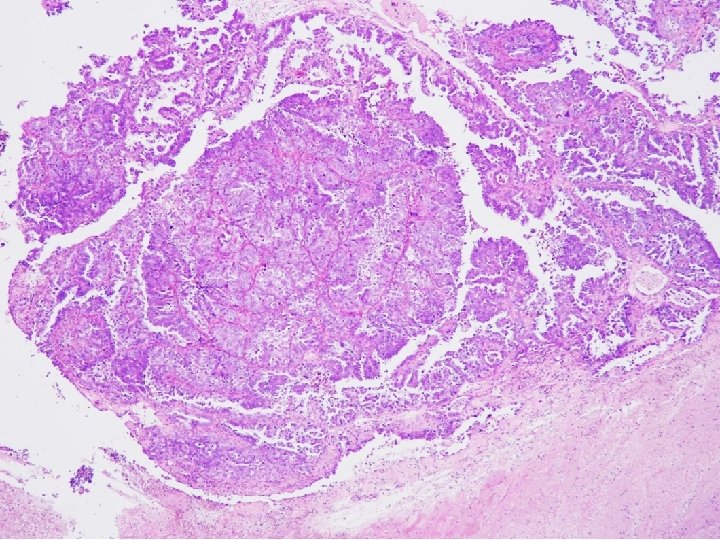

Tissue from uterine cervix, biopsy; Poorly differentiated adenocarcinoma with 1) sheets and papillary features 2) tubulocystic pattern 3) frequent clear cell feature c/w CLEAR CELL CARCINOMA

CYTOPATHOLOGIC FEATURES OF CLEAR CELL CARCINOMA • Arrangement – Cells are isolated, in loosely cohesive groups and in syncytial tissue fragments; hobnail pattern may be present • Cells – Medium to large with poorly defined cell borders; moderate to high N/C ratios; round, polygonal to hobnail type • Nuclei – Large, round, often eccentric, very pleomorphic; coarsely granular to smudgy chromatin; nucleoli are inconsistent; multinucleation • Cytoplasm – Variable, scant to abundant, clear to pale, weakly staining either eosinophilic or cyanophilic • Background – Clean, bloody or inflammatory; naked nuclei Color Atlas of DDx in Exfoliative and Aspiration Cytopathology, Kini